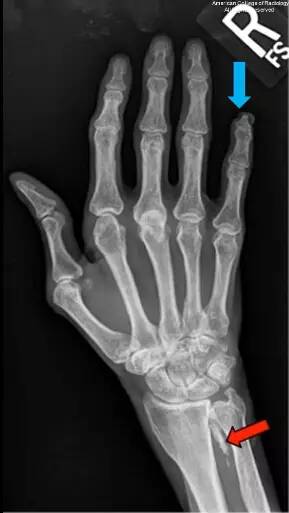

图 2 为右手斜位,可见临近尺骨近端一线性钙化(蓝色箭头)。腕部背侧仍可见钙化(红色箭头)。第一和第三掌指关节可见半脱位

图 3 为右手后前位,可见小指肢端骨质溶解(蓝色箭头)。仍可见软组织钙化灶(红色箭头)。肌萎缩明显